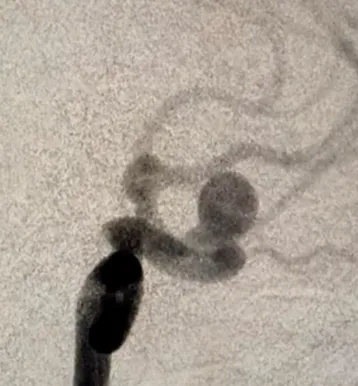

Аневризми мозкових артерій — це патологія судин, при якій відбувається випинання стінки артерії. За формою випинання розрізняють мішотчаті та веретеноподібні (фузіформні) аневризми. Причина появи аневризм достеменно не відома. Серед етіологічних факторів можуть виступати вроджена схильність (дефекти м’язового шару стінки мозкових судин); атеросклеротичні (поєднуються із вродженими дефектами стінки мозкових судин); емболічні, інфекційні, травматичні фактори.

МРТ головного мозку, церебральна ангіографія, КТ-ангіографія.

У разі виявлення неускладнених аневризм проводиться планове нейрохірургічне втручання методами кліпування аневризми чи балонної ангіопластики (ендоваскулярне закриття випинання стінки судини).

Вибір тактики лікування залежить від загального стану пацієнта, анатомічних особливостей та розташування аневризми, моменту виявлення по відношенню до розвитку ускладнень (до розриву чи після розриву).